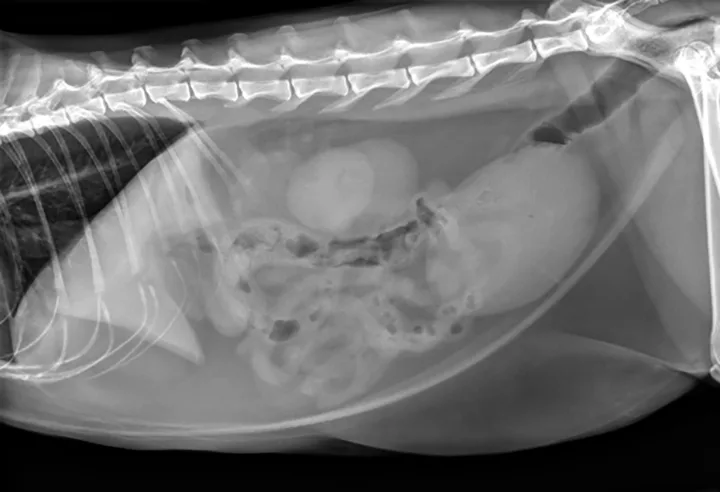

Figure 1. The urinary bladder appears large and there is bilateral renomegaly in this right lateral view; dystrophic mineralization is present in the right kidney.

At initial examination, Ivan was alert and responsive with heart rate, respiratory rate, and temperature within normal limits. He was estimated to be 5% dehydrated and had a large, firm, nonexpressible bladder. He was sedated with 0.015 mg/kg IV of buprenorphine, 0.2 mg/kg IV of midazolam, and administered a total of 2.5 mL of propofol IV for urinary catheter placement. A 5-French red rubber catheter was placed with slight resistance and maintained in place with butterfly tape and stay sutures. A CBC, serum chemistry panel, and plain abdominal radiographs (Figure 1) were performed.

2. Feline idiopathic cystitis is commonly associated with urethral obstruction in male cats.1,3,4 Because this patient had a previous episode of urethral blockage—and because the 2 episodes were close together—perineal urethrostomy was a valid option after correction of azotemia. Plain abdominal films should be taken in feline idiopathic cases to look for cystic or urethral calculi.<sup5sup>